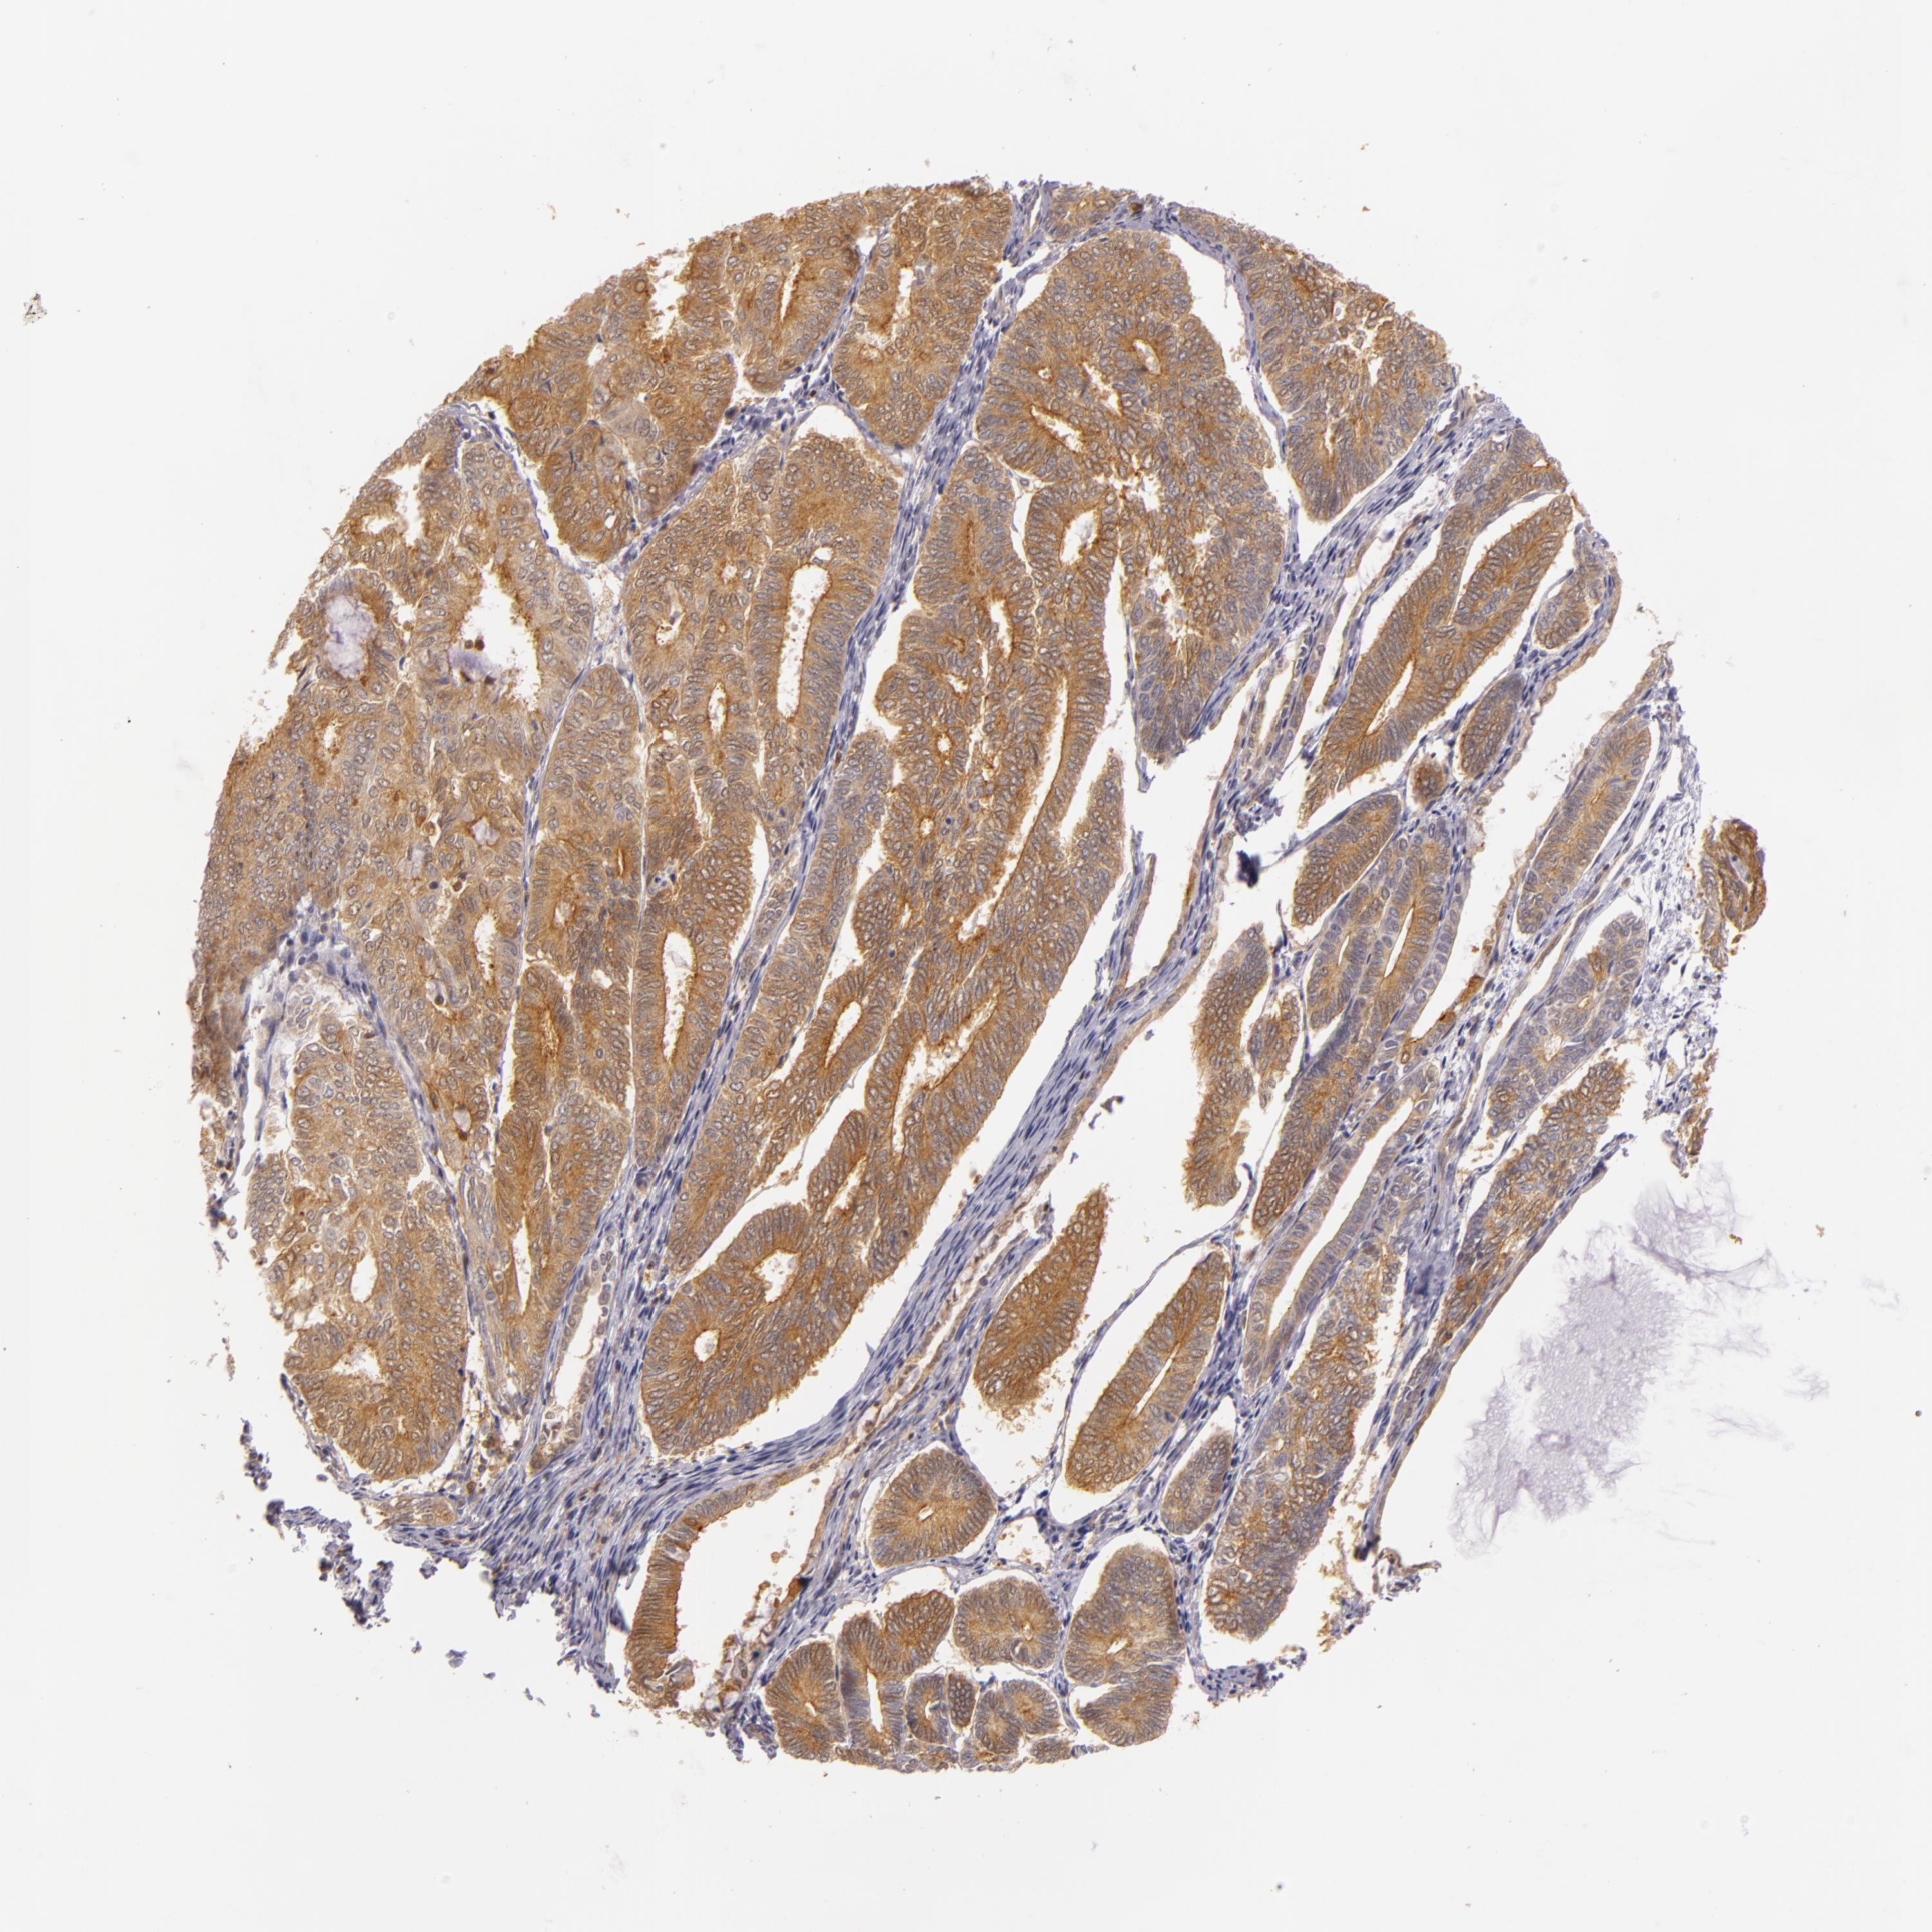

ENDOMETRIAL CANCER - Protein expressioni

A mouse-over function shows sample information and annotation data. Click on an image to view it in a full screen mode. Samples can be filtered based on level of antibody staining by selecting one or several of the following categories: high, medium, low and not detected. The assay and annotation is described here.

Note that samples used for immunohistochemistry by the Human Protein Atlas do not correspond to samples in the TCGA dataset.

Antibody stainingi

Antibody staining in the annotated cell types in the current human tissue is reported as not detected, low, medium, or high, based on conventional immunohistochemistry profiling in selected tissues. This score is based on the combination of the staining intensity and fraction of stained cells.

Each image is clickable and will lead to virtual microscopy that enables deeper exploration of all samples and also displays staining intensity scores, fraction scores and subcellular localization as well as patient and tissue information for each sample.

Antibody HPA001749

Staining

High

Medium

Low

Not detected

Intensity

Strong

Moderate

Weak

Negative

Quantity

>75%

75%-25%

<25%

None

Location

Nuclear

Cytoplasmic/membranous

Cytoplasmic/membranous,nuclear

Adenocarcinoma, NOS